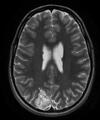

Based on the diffusion-weighted image (DWI) and clinical presentation, this patient has an ischemic stroke in the left lateral medulla and left cerebellar hemisphere, regions supplied by the left posterior inferior cerebellar artery (PICA). This can manifest as lateral medullary syndrome as described in the clinical scenario. Occlusion of an anterior inferior cerebellar artery can cause a lateral pontine syndrome, which manifests as nystagmus, dysarthria, hemi-ataxia, hearing loss, and facial paralysis. Occlusion of a superior cerebellar artery (supplies the superior cerebellar peduncle, the cerebellar hemisphere, and the cerebellar nuclei) can present as headaches, vertigo, nausea, and diplopia.